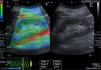

A case of light chain renal amyloidosis with moderate interstitial fibrosis (25%). The greyscale ultrasonography image showing moderate increased parenchymal echogenicity with preserved cortico-medullary differentiation, the left one showing color-coded US – elastography image showing mixed green-blue scale and the sinusoidal wave of compression and decompression seen in inferior aspect of image. The circles indicate the region of interests (ROIs). The upper ROI is on the parenchyma and the lower ROI is on renal fat sinus. The radial line on the sinusoidal wave indicates the end measurement (SI=2.74).